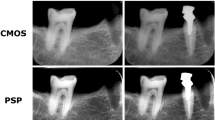

Examples of an initial radiograph, secondary radiographs for each exposure setting, and subtracted radiographs are shown in Fig. 4 (0.32-s group). The anatomical structures remained visible, and the areas of bony change were sometimes invisible in the subtraction images created with secondary radiographic images that were taken at exposures of 0.04 and 0.02 s.

Examples of initial, secondary, and subtraction images in the 0.32-s group. The secondary images were taken with a 10-mg bone chip. Top row initial radiographic image. Middle row secondary radiographic images taken at various exposure times. Bottom row subtraction images created by subtracting the secondary images from the initial image. The anatomical structures remained visible on the subtraction images prepared from radiographs taken with exposure of 0.04 s, but the areas of bony change were no longer visible with exposure of 0.02 s

In this study, the 0.32-s group subtraction images created with an exposure time of 1/8 of the initial radiograph (0.04 s) showed anatomical structures but the area of the bone chip was clearly discernible. However, when the exposure time was reduced to 1/16 of the initial exposure time (i.e., 0.02 s), sometimes bone changes were no longer visible in the subtraction image. In the 0.16-s group, subtraction images that were created with secondary images reduced to 1/8 of the exposure time of the initial image (i.e., 0.02 s) did not show bone changes. The limited visibility of bone changes on subtraction images taken at these reduced exposures may be related to the exposure time of the secondary radiographs. An exposure time of 0.02 s is too short for the secondary radiographs. It may be possible to further reduce the exposure time for the initial image, but if it is reduced by too much, the image becomes “noisy”. Even with short exposure times, digital radiographs contain noise of various levels, which can arise from fluctuations in X-ray photons, low radiation doses, or instability/deficiencies in the electronics of the detectors. On the reduced exposure time images, the image-to-noise ratio could increase and this may limit how far exposure times can be reduced while still yielding useful images.